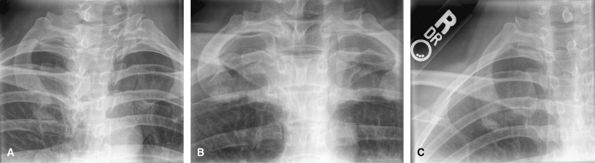

Clavicles

Good for clavicle fractures. Medial clavicle fractures

can be difficult to see. Consider CT for possible medial clavicle

fractures.

![]() |

|

Figure 18 (A) AP, 0-degree tube angle. (B) AP, 10-degree cephalad angle.